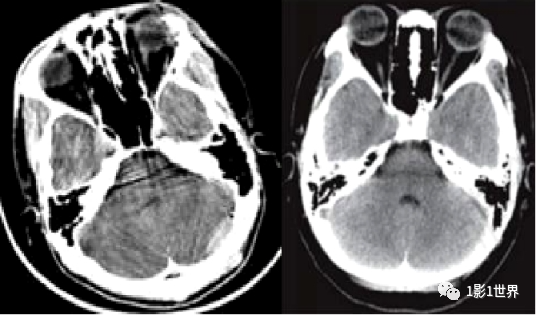

类似硬膜下血肿的运动伪影

就伪影形成的原因,有设备本身因素,有扫描条件设置因素,有患者因素。正面,展示几种临床上常见的伪影,并分析其形成的原理,克服的办法。规范预热;定期空气校准;维护和保养;检测硬件故障,并更换。也叫条纹状伪影,表现为图像上低密直线,无规律出现。插值算法是导致这类伪影的主要原因。伪影的面积比,要随螺距的增大而增大。致密物体之间的条纹状低密度影;如头部后颅窝亨氏暗区,就是典型的更化束伪影。密度相差较大的物体之间的条带状高低密度影;如胃内气体较多时,肝胃之间的伪影。薄层扫描,厚层重建;改变体位